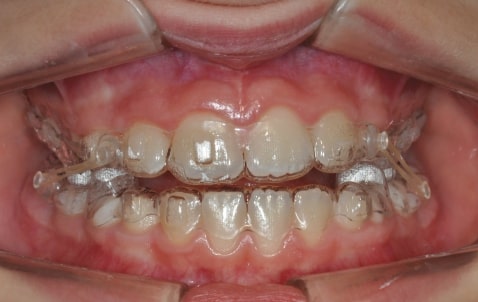

Treatment details

AngelAligner KiD 1 (aligners changed every 10 days)

• Upper frenulum surgery

• Class 1 both sides

• Overjet/Overbite Correction

Treatment progress